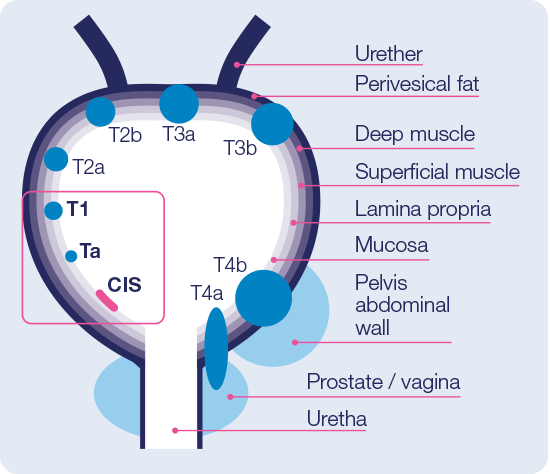

Bladder Cancer Hexvix

https://www.hexvix.com/sites/www.hexvix.com/files/images/bladder-cancer-tumor-classification-2.png